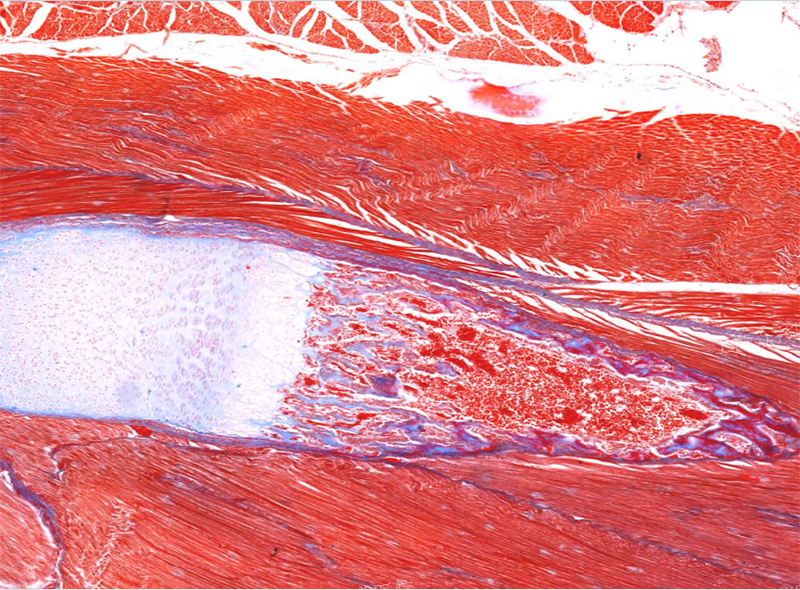

靜脈血栓